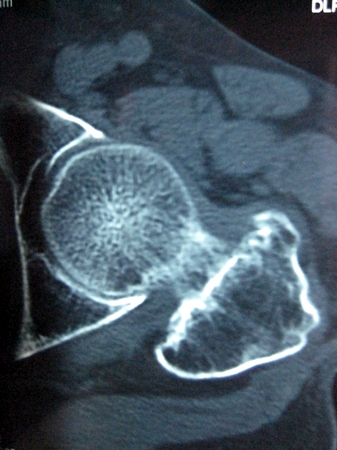

以下是引用lkc8963在2008-12-19 21:19:00的发言:[br]左?右?患侧大转子上移,股骨颈骨质浓杂,髋周见多发条片状骨化影,以小转子为著,多为陈旧性股骨颈骨折后改变并骨化性肌炎.请咨询既往史!